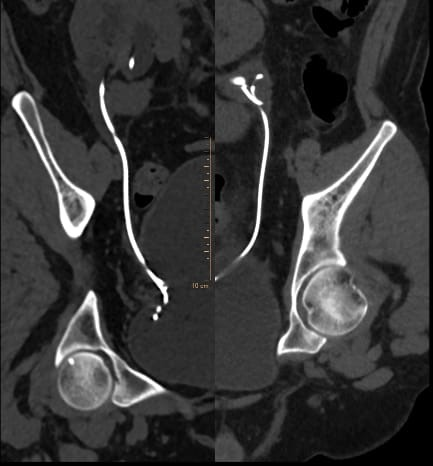

Postoperatively, the patient was vitally stable without any complications. The drain was removed on the third day, and catheter removal was performed after 7 days. Low-dose KUB CT was performed after 6 weeks for any remaining stone fragments, suggesting complete clearance , and bilateral DJ stent removal was performed after 6 weeks

Figure 4:- Post operative CT KUB suggestive of bilateral DJ stent in-situ with no  residual stone fragments